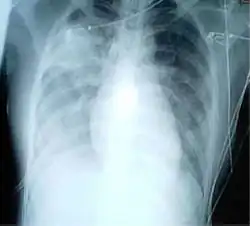

Une radiographie pulmonaire montrant des opacités dans les deux poumons, indicatives d'une pneumonie, chez un patient atteint de SRAS.

L’imagerie radiologique occupe une place importante dans le diagnostic initial de syndrome respiratoire aigu sévère puis dans le suivi de l’efficacité du traitement. Les images les plus typiques comportent une localisation périphérique prédominante, des opacités alvéolaires unilatérales et focales progressant sous traitement vers une atteinte unilatérale multifocale ou bilatérale. Il n’existe ni excavation, ni adénopathie, ni épanchement pleural. Le scanner thoracique est un examen complémentaire qui permet en général de préciser les signes de pneumopathie sévère.